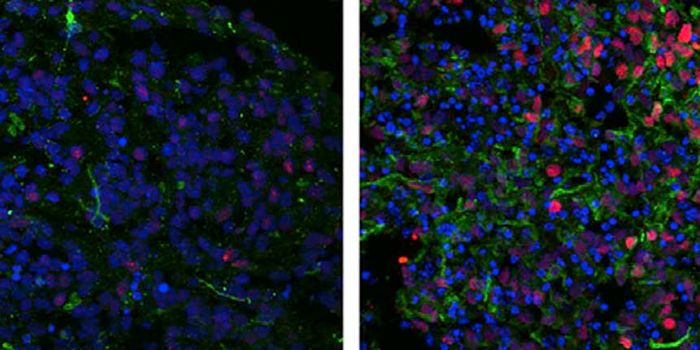

MAR 03, 2016Cell & Molecular BiologyFor the first time, scientists have turned skin cells into cancer-hunting stem cells that destroy brain tumors known as ...